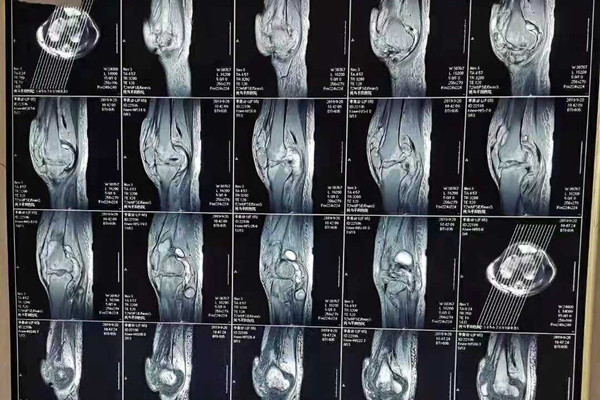

西医认为骨结核是由结核杆菌侵入骨或关节而引起的化脓性破坏性病变。而祖国医学因其病发于骨或关节,消耗气血津液,致使后期形体嬴瘦,正气衰败,缠绵难愈,故名骨痨。

患上骨结核病情还是非常严重的,如果不及早进行治疗,则会引起病人瘫痪,这主要就是由于结核病变对骨头的侵蚀,导致骨质破坏的非常严重,继而可能会出现瘫痪的情况。